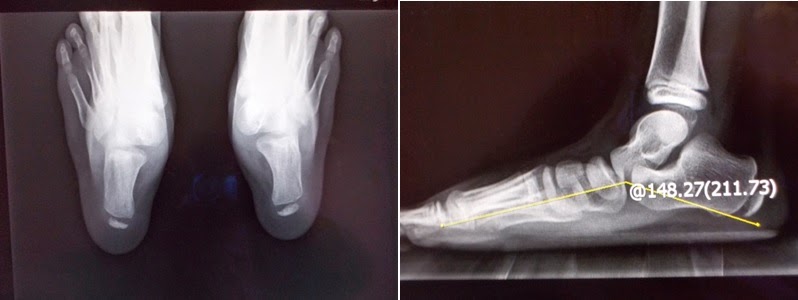

赤腳走路更可看出其特有的內傾(pronation)步態;以特定角度照的X光,更可看到某些負重骨骼間的相關角度有差異,或關節骨頭的一些變化(如圖),診斷並不困難。

(左圖:扁平足並足底筋膜炎. 右圖:扁平足 因距-舟狀骨關節退化及跗底肌腱炎 腳痛)